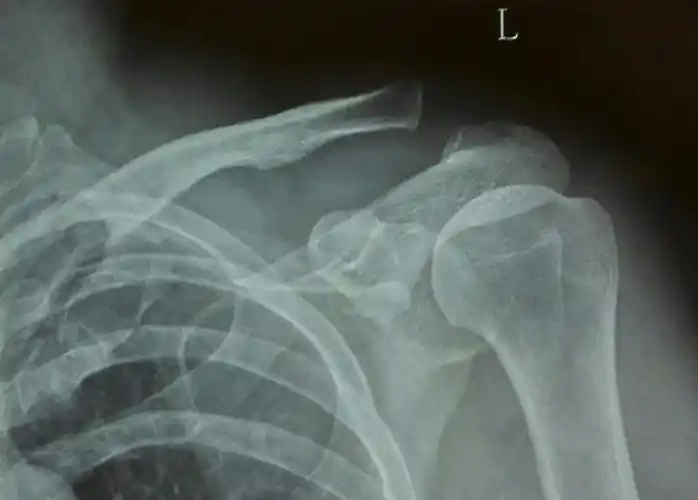

左肩锁关节脱位endbutton固定